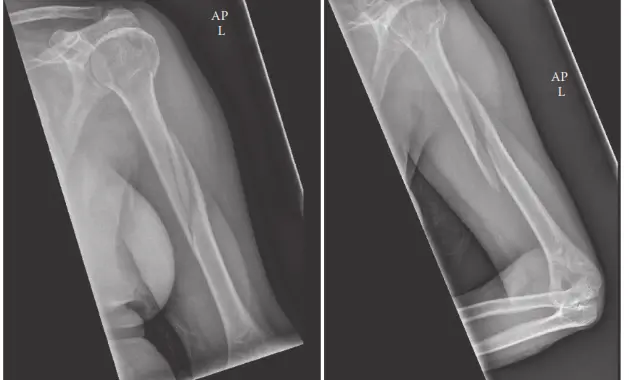

- الأشعة السينية (X-rays): هي الخطوة الأولى والأساسية في التشخيص. يتم التقاط صور للأشعة السينية من عدة زوايا (أمامية خلفية وجانبية) للذراع بأكملها، بما في ذلك مفصلي الكتف والكوع. تساعد هذه الصور في تأكيد وجود الكسر، وتحديد نوعه (عرضي، مائل، حلزوني، مفتت)، وموقعه، ودرجة إزاحته.

- التصوير المقطعي المحوسب (CT Scan): قد يُطلب التصوير المقطعي في حالات الكسور المعقدة أو المفتتة، أو إذا كان هناك اشتباه في امتداد الكسر إلى المفاصل (على الرغم من ندرة ذلك في كسور منتصف العضد). يوفر التصوير المقطعي صورًا ثلاثية الأبعاد أكثر تفصيلاً للعظم، مما يساعد في التخطيط الجراحي الدقيق.

يُعد التخطيط المسبق للعملية الجراحية أمرًا بالغ الأهمية. يقوم الأستاذ الدكتور محمد هطيف بتقييم صور الأشعة السينية والتصوير المقطعي بدقة، ويختار نوع الغرسة (الشريحة أو المسمار) وحجمها المناسبين، ويناقش المخاطر المحتملة (مثل إصابة العصب الكعبري، عدم الالتئام، العدوى، الحاجة إلى جراحة مراجعة) مع المريض.